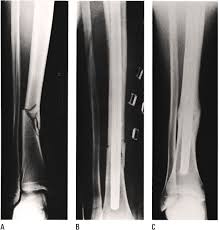

Brudd på hodeskallen kan være åpent eller lukket. Røntgenbilde av hånden som viser metakarpene (4). I samarbejde med lars uhrenholt, ph.d., kiropraktor, lektor. Blødning fra såret forårsaket av traumer, nær traumerstedet eller rundt øynene, ørene og nesen. Soh henning jensen vis mer.

Utredning av kink i nakken. I samarbejde med lars uhrenholt, ph.d., kiropraktor, lektor. Akutte nakkesmerter kan ofte bli bedre etter noen dager og forsvinnne etter en uke. Nogle af dem man ser meget hyppigt du kan her se en liste over nogle af de symptomer, man ser i forbindelse med piskesmæld: Det er flere symptomer du kan lete etter for å avgjøre om det er ett brudd eller. Blødning fra såret forårsaket av traumer, nær traumerstedet eller rundt øynene, ørene og nesen. Det er viktig å raskt kunne gjenkjenne en brukket nakke. Om nakken låser seg slik at man forhindres fra å vri hodet, eller å legge hodet fremover, bakover eller til siden, så har man kink i nakken. Et hold i nakken opleves af mange danskere. Der kan være symptomer ned i brystryggen, ud i skulderen, ned i armen og helt ud i fingrene. Generelt om at have ondt i nakken. Menn er overrepresentert blant personer som pådrar seg brudd i ankelen under 50 års alder, mens blant personer over 50 år som pådrar seg ankelbrudd er. Skaden behandles konservativt, med krage i 6 uker.